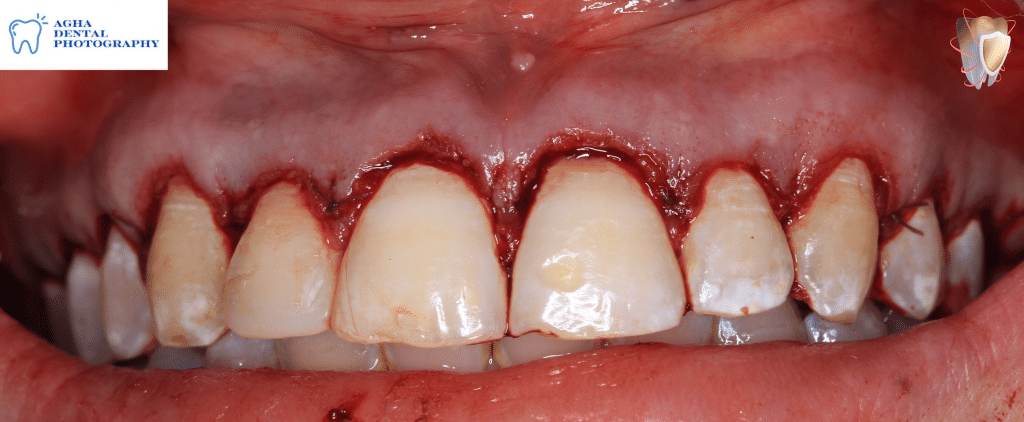

Rechecking biologic space confirming that it is insufficient "less than 2mm"

Ostectomy for correction of insufficient biologic space using rose head stone bur

Osteoplasty to reshape the labial plate of bone using a flame shaped stone bur

After finishing ostectomy & osteoplasty creating sufficient even biologic spaces of 2mm "from CEJ to crest of alveolar bone" & correcting thick bony ledges & irregular architecture of labial plate of bone

Flap suturing using 5/0 polyglycolic "vicryl" sutures with single sling suturing technique

After finishing flap suturing